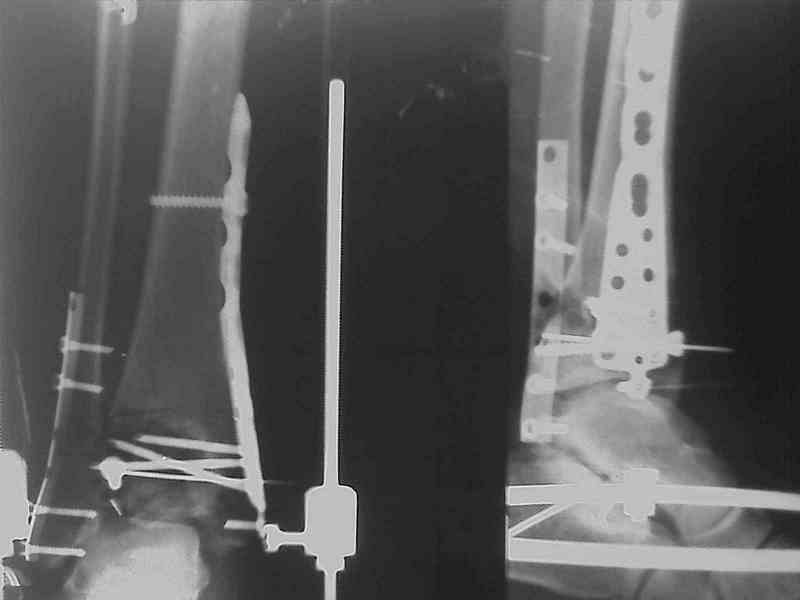

Снова приветствую вас, коллеги. К моменту вступления в обсуждение

аксакалов, операция была,  увы, выполнена(31.10.07.) Начали с доступа к

наружной лодыжке, произвели ее фиксацию спицами, развернули кусок

заднего края, наложили дистрактор,  затем произвели дистракцию, фиксацию

спицами дистального эпиметафиза б/бк,Рентгено-контроль. синтез наружной

лодыжки 1/3пластиной. из двух коротких разрезов сформирован канал под

медиальную тибиальную пластину  LCP. Края ран ушиты без натяжения.

Прочувствовать жесткость фиксации винтами с угловой стабильностью не

удалось, поэтому дистрактор оставлен на энное время.

На представленных R-снимках не окончательный вид после остеосинтеза.

Дистальная опора давила на стопу, пришлось ее  сместить проксимально, в

рез-те чего, она закрыла щель сустава, последние снимки не информативны.